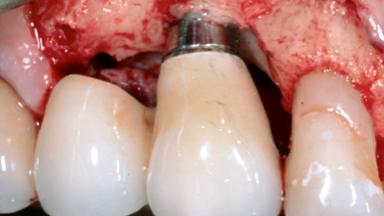

Open-Flap Debridement for the Management of Peri-Implant Mucositis Associated with Excess Cement

A 79-year-old female patient was referred to the Department of Periodontology of the University of Bern, Switzerland by her private dentist in May 2019. She had been rehabilitated in May 2005 with two tissue-level implants (Institut Straumann AG, Basel Switzerland) at sites 13 and 15, supporting a three-unit cemented fixed dental prosthesis (FDP). The metal-ceramic FDP had been cemented permanently with a glass-ionomer cement (Ketac Cem; 3M ESPE, Seefeld, Germany). Implant 13 had been diagnosed with peri-implant mucositis by the referring dentist in the course of regular supportive therapy. The patient was in good general health, did not smoke, and exhibited good self-performed plaque control.